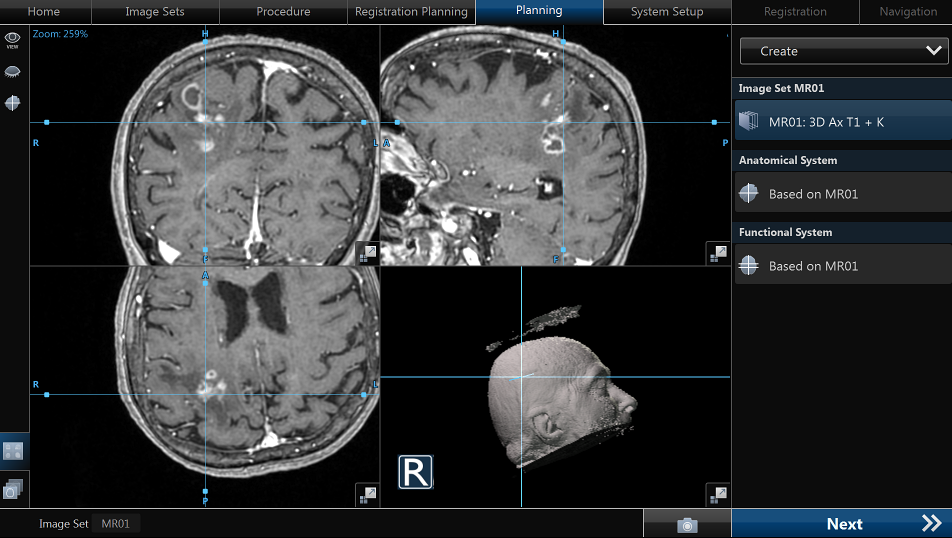

IRM cerebral cu substanță de contrast – metoda de elecție. Limfoamele sunt leziuni cu hipersemnal T2-FLAIR și hiposemnal T1, imprecis delimitate, cu contrast intens, adesea periventriculare si cu aspect caracteristic de difuzie (ADC). Poate mima glioblastomul sau metastazele cerebrale.

- Biopsie cerebrală stereotactică – esențială pentru diagnostic histologic.

Recidiva este frecventă, în special în primii 2-3 ani. Monitorizarea periodică prin IRM cerebral este esențială. În recăderi, se pot utiliza terapii de salvare (temozolomid, radioterapie, transplant).